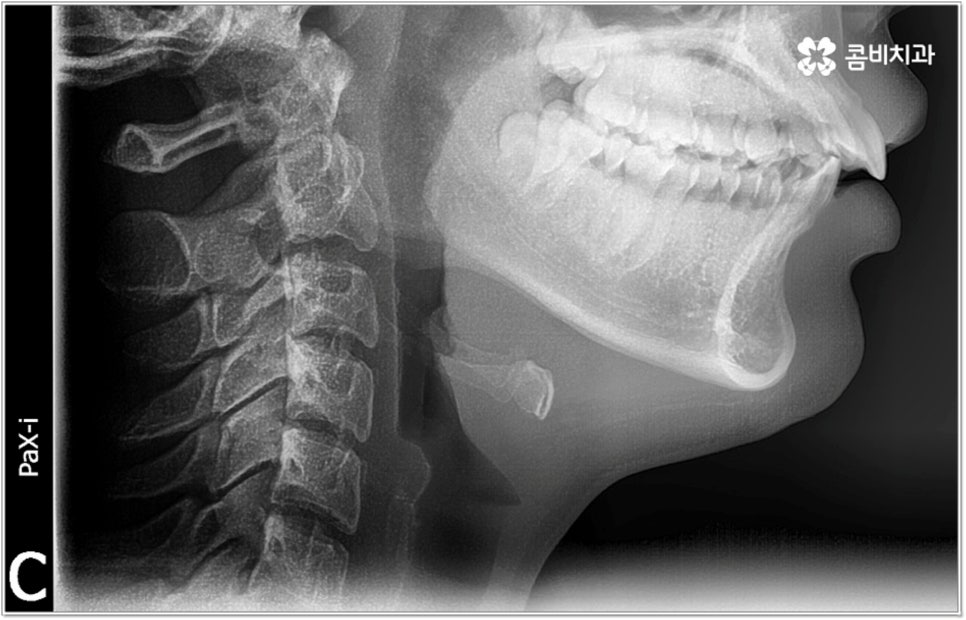

무리하지 않고 돌출입치아교정 과정을 진행하기 위해서는 먼저 꼼꼼한 검진 및 분석에 따른 철저한 맞춤 치료 계획 수립이 중요하다고 할 수 있는데요. 특히 3D CT 및 모르페우스 시스템을 통해 현재 아이의 치열이나 연조직, 상하악 관계 등을 자세히 살펴보고 안모 분석 후 교정 치료가 끝난 예상 모습을 시뮬레이션해서 보여주면 환아의 흥미를 유발하고 앞으로 진행될 사항에 대한 이해도를 높여줄 수 있어 긍정적인 영향을 줄 수 있으니 정밀 검진 장비를 갖추고 숙련된 의료진이 치료하는 치과에서 돌출입치아교정 과정을 진행하시길 권유드리고 있어요.

성장기 교정의 경우 턱성장 추이에 맞추어 섬세하게 치아 이동 속도를 결정해야 하므로 구강 검진 외에도 성장판 검진 등을 통해 아이의 전반적인 발달 상황에 대한 유기적인 이해를 바탕으로 치료를 하는 경험 많은 담당의 선생님께 시술을 맡기실 필요가 있습니다. 또한 이렇게 뛰어난 노하우와 기술력을 갖춘 것 뿐 아니라 사전 상담, 전 교정 과정 그리고 사후 관리에 이르기까지 지속적인 소통을 통해 불편한 점이 없는지 세심하게 살피고 개개인의 상황 및 구강 건강을 전체적으로 신경써서 케어해 주는 의료진과 함께 한다면 환아 뿐 아니라 부모님의 입장에서도 더욱 안심이 되고 좋을 거예요.